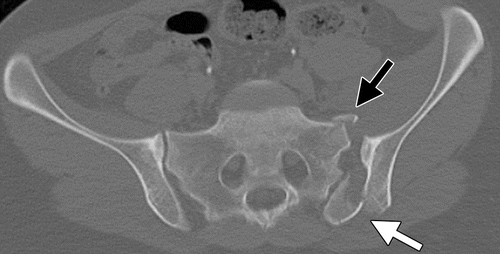

28세 여성이 자전거 사고로 응급실에 도착했다. 간파열, 신장손상, 골반 골절이 확인되었다. 수술 전 골반 컴퓨터단층촬영 결과이다. 응급 수술 후 호흡곤란과 의식 저하가 발생하였으며, 상하지와 복부에 점상출혈이 나타났다. 수술 후 점상출혈, 가슴 X선 사진, 혈액 검사 결과이다. 원인이 무엇인가?

• 다발성 외상 환자의 골반 컴퓨터단층 촬영에서 골반 골절이 확인된다.